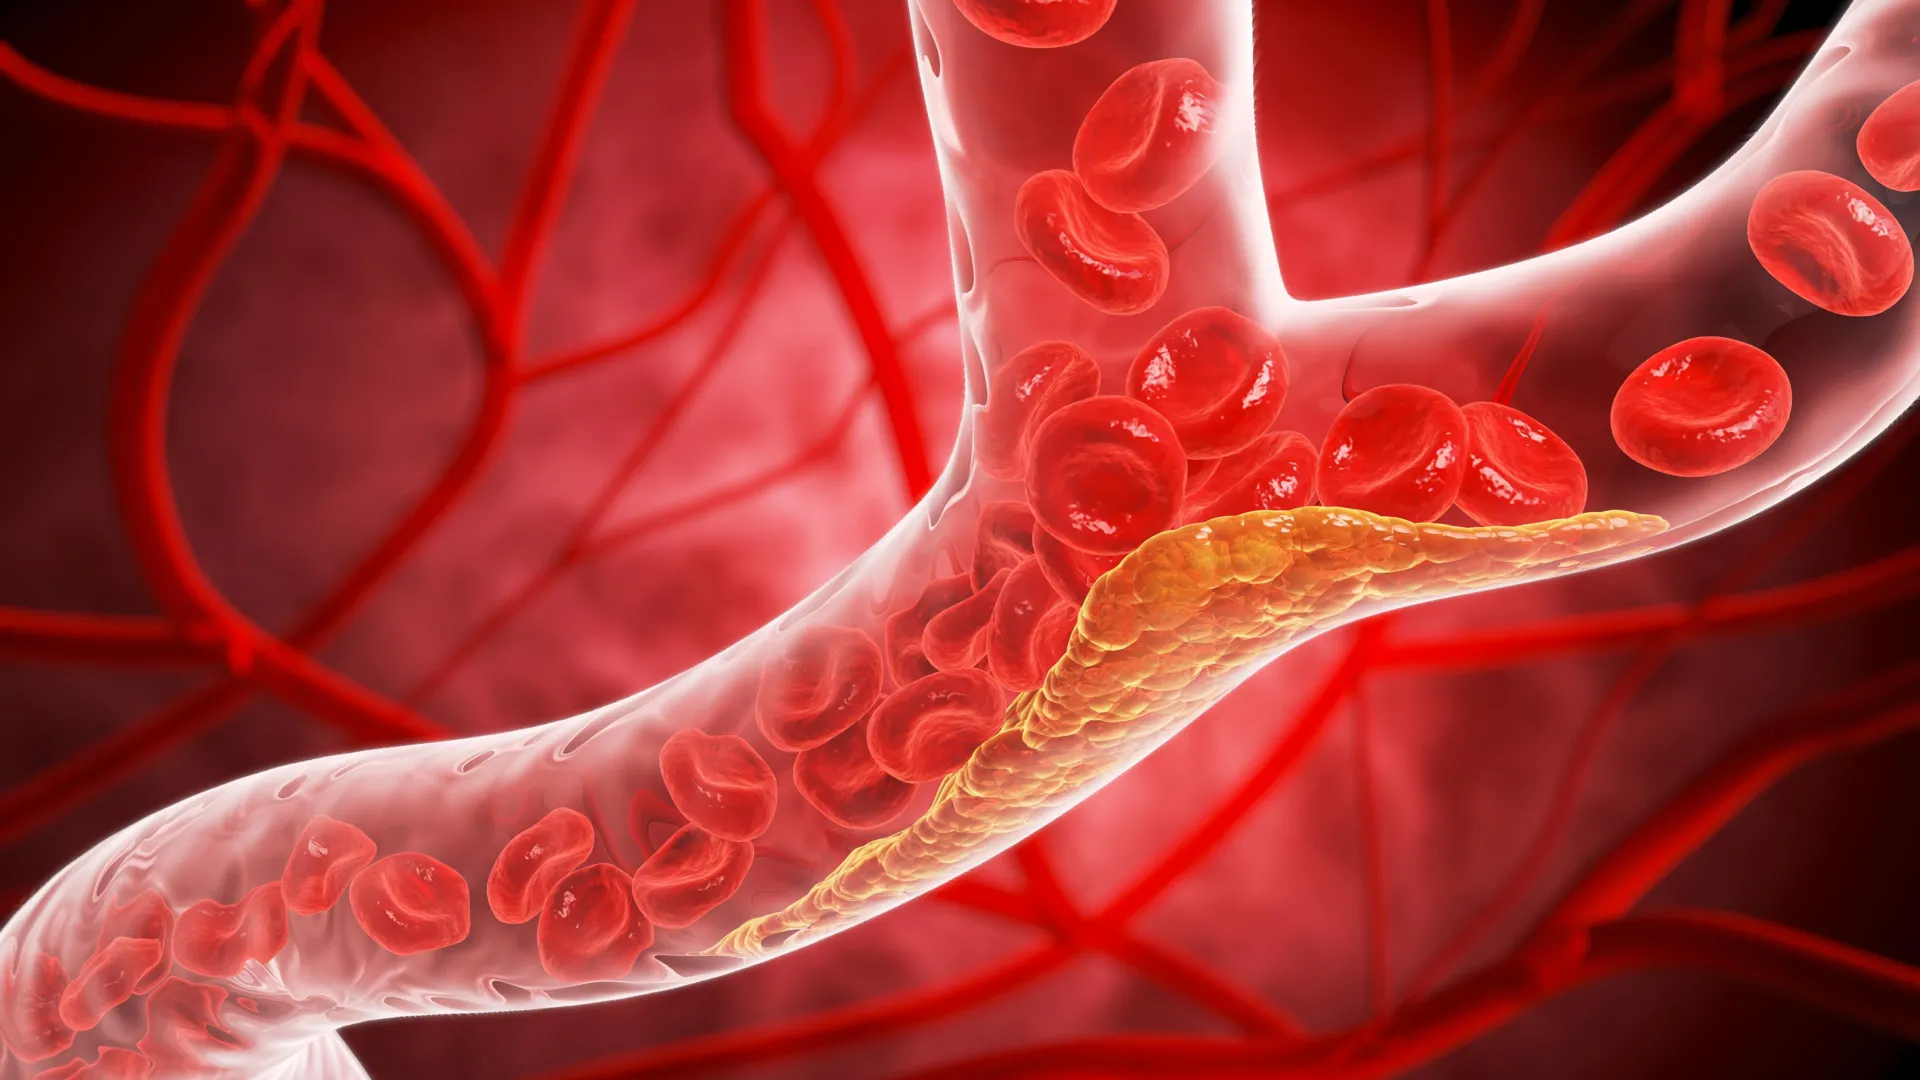

Oral PCSK9 Inhibitor Demonstrates Profound LDL Cholesterol Reduction, Signifying Major Advance in Cardiovascular Prevention

A groundbreaking experimental oral therapy, known as enlicitide, has achieved remarkable success in significantly lowering levels of low-density lipoprotein (LDL) cholesterol, frequently termed "bad" cholesterol, by an average of 60%…